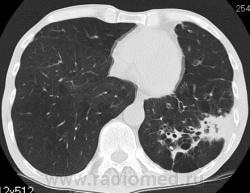

КТ - ОГК.  Ваше мнение коллеги?

На фоне консолидации полость без содержимого. Может быть всё что угодно, что сопровождается деструкцией. Нужны ещё томограммы в лёгочном окне.

Изображения выставлены все. Ваше мнение уважаемые коллеги?

Нет опыта работы на цифровых аппаратах: дефекты правого нижнего лёгочного поля объясняются артефактами?

Предположу аспергиллез

Почему? Признаки?